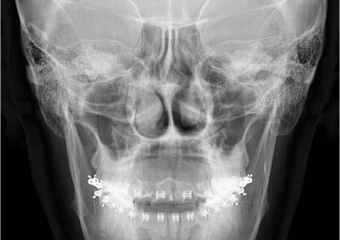

Telerradiografia inicial